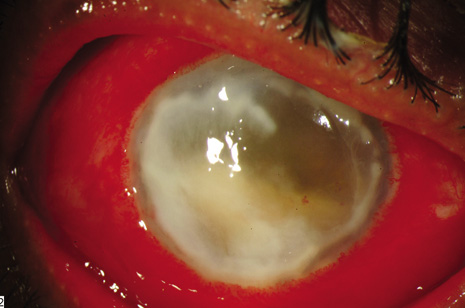

This category of endophthalmitis is similar to acute postoperative endophthalmitis in that these patients manifest a sudden onset of pain, visual loss, conjunctival congestion, purulent bleb involvement, and the typical diagnostic features of acute-onset endophthalmitis (Fig. 8).10,11,104 Risk factors for this category of endophthalmitis include a history of conjunctivitis, contaminated topical glaucoma medications, the use of contact lenses, and inferior filtering bleb.10,104 The incidence of bleb-related endophthalmitis after a glaucoma-filtration procedure with mitomycin C may be higher than for trabeculectomy without antifibrotic agents.104 The organisms frequently involved in this type of endophthalmitis include streptococcal species8,71 and Hemophilus influenzae. Because of the frequency of these virulent organisms and the generally poor visual acuity outcomes, PPV and intraocular antibiotics are often considered as the initial approach for conjunctival filtering bleb-associated endophthalmitis.

Fig. 8. Delayed-onset endophthalmitis associated with glaucoma filtering blebs. Organisms invade the bleb initially and spread to involve intraocular fluids and tissues. This patient shows characteristic purulence of the filtering bleb, conjunctival congestion, hypopyon and fibrin in the pupil. Streptococcus pneumoniae was isolated from the vitreous specimen.

It is important to distinguish between a localized bleb infection (blebitis) and true endophthalmitis associated with an infected filtering bleb.11 The former category can be treated with intensive topical, subconjunctival, and possibly systemic antibiotics while the latter category can be treated in a manner similar to acute-onset postoperative endophthalmitis (Fig. 9).

Fig. 9. Bleb-associated endophthalmitis occurring two years following glaucoma filtering surgery. Left: Marked purulence of the bleb, hypopyon, and fibrin in the pupil. Visual acuity was reduced to hand motion. The patient was treated with a vitreous tap and injected with intravitreal antibiotics. Right: Coagulase-negative staphylococcus was isolated from the vitreous. Final visual acuity was 20/400 because advanced glaucomatous disease limited visual recovery.